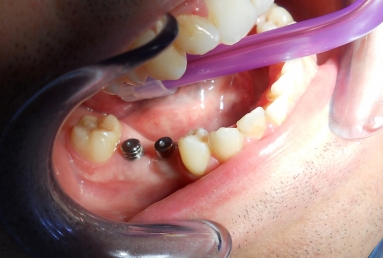

Initial situation: two missing teeth, second lower premolar and first lower molar. two dental implant are integrating in the mandibular bone for 4 months, then, gingival healing caps are applied for 3 weeks. an impression is taken for the dental lab in order to manufacture 2 porcelain fused to metal crowns. they will be screwed directly in the implant body.